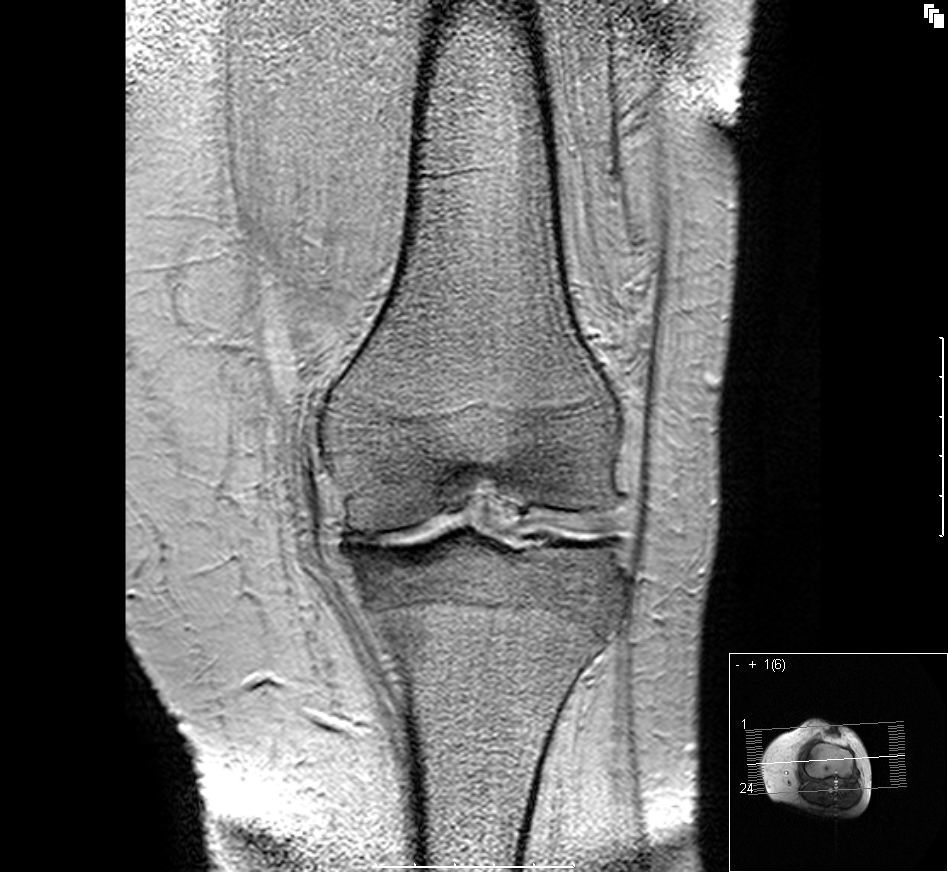

退化性關節炎是最常見的關節疾病,特徵是軟骨損壞並擴散到所有的關節結構,尤其是骨頭與滑膜組織的部份。覆蓋在關節最外層骨質上且可互相滑動的軟骨會越來越薄、進而碎裂,最後完全消失,引發疼痛與喪失行動能力的嚴重殘障。

退化性關節炎的診斷方式是臨床檢查,醫生透過關節 X 光照射來觀察連結骨頭的關節空隙縮小情形。為了觀察病情的嚴重性與惡化速度,尤其是非脊柱部分的狀況,最好每一到兩年定期檢查一次。

– 退化性膝關節炎與退化性髖關節炎:分別佔 65 歲至 75 歲人口的 30% 與 10%,它們最易使人喪失活動能力,因為受到影響的是承載人體重量的大型關節。